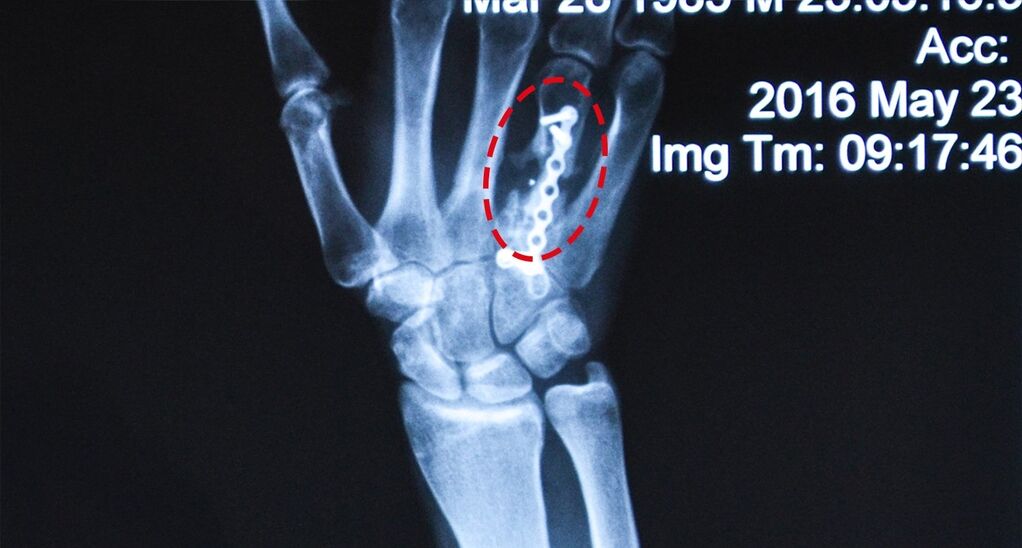

Ліва рука:

– незрощення перелому 4 п’ясної кістки.